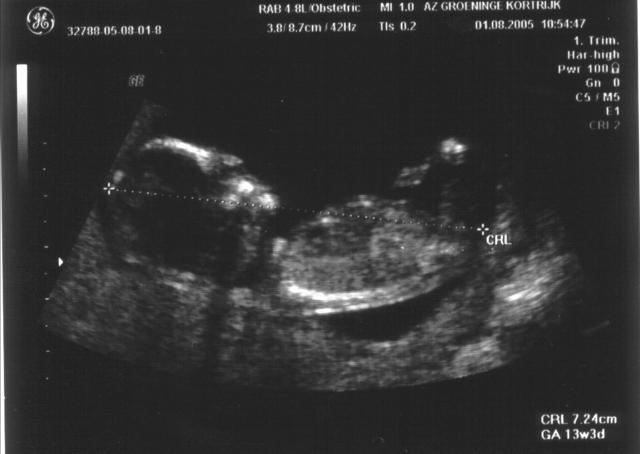

Nu begint alle goed te groeien, op 13 weken zitten we al aan 7,2 cm